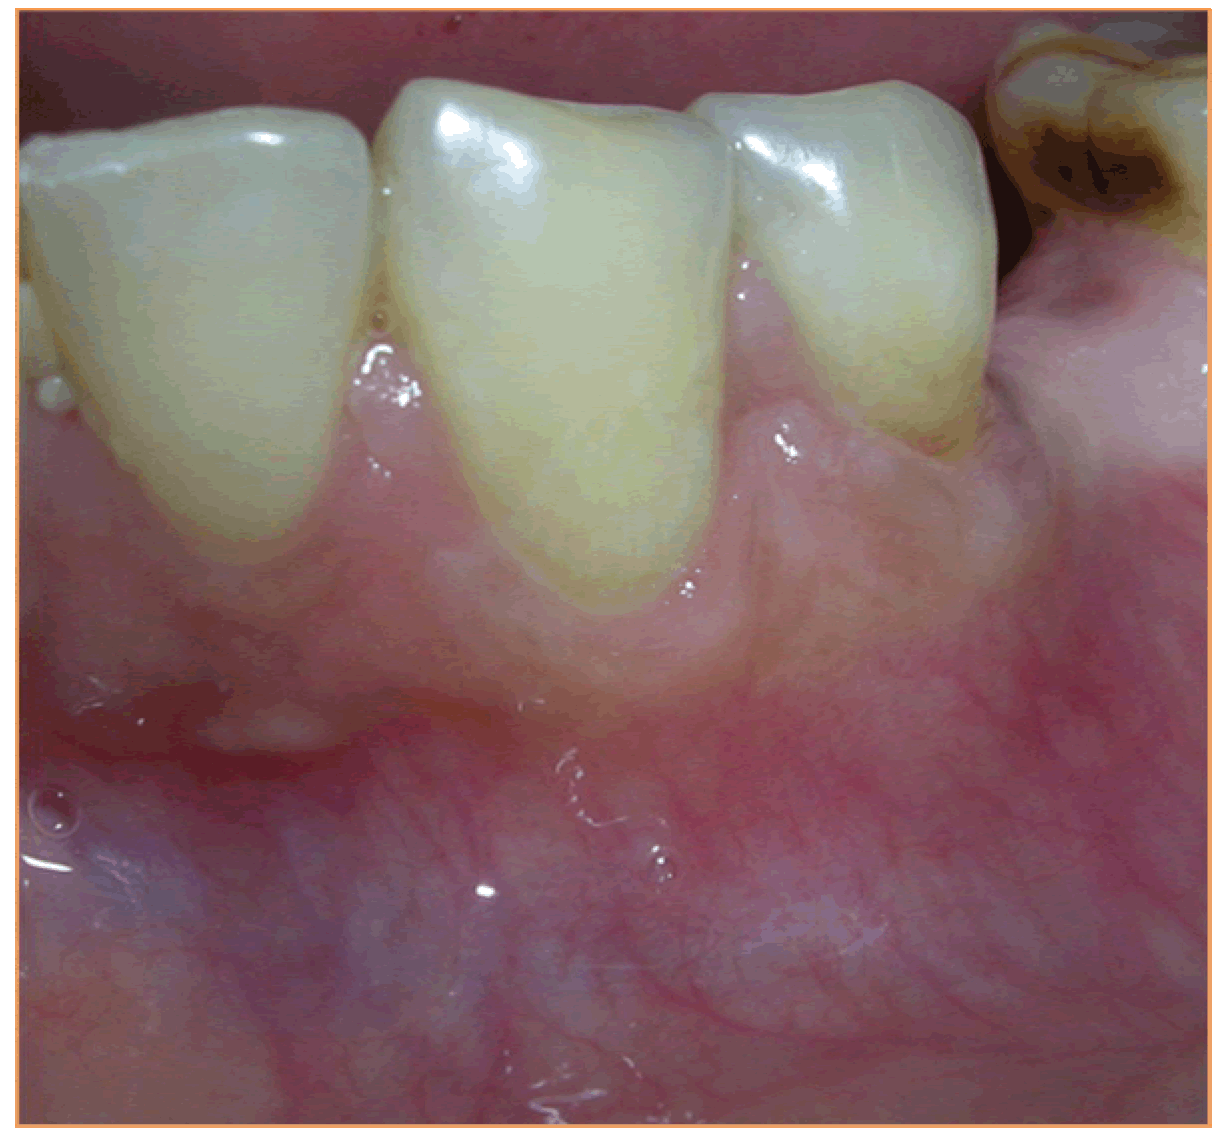

Case 3: A 35-year-old female patient presented and her main concern was the gums 'going down' in relation to the lower teeth on the left side. She was diagnosed as a case of Millers Class II recession in relation to 34 and 35 (Figure 6). This case too was treated using the pouch and tunnel technique with placement of CTG procured from the palate. The donor site appeared normal in color and healthy after four weeks and the recipient site was healthy with excellent color match with adjacent tissues in all four cases. These results were stable and maintained at the time of review, 12 months in Case 1 (Figure 7), 18 months in Case 2 (Figure 8), six months in Case 3 (Figure 9). The mean root coverage achieved in these cases was an average 90% which is close to the mean root coverage of 91.6% in the Zabaluigi study.

Figure 6: Millers Class II recession on 34 and 35.